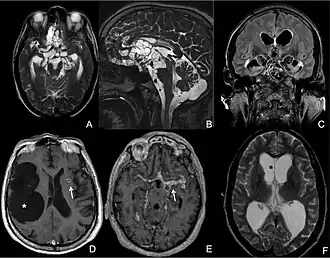

CT scans and magnetic resonance imaging (MRI) give objective information about the number and pattern of lesions, the stage of healing, and how the immune system is responding to the parasites.[19] MRIs are better for evaluating different spatial planes and provides clearer images, which helps in identifying small lesions at the back of the brain or near the skull that may be missed on CT scans. CT scans are more sensitive at detecting calcium buildup in the brain due to its ability detect calcifications in the brain.[30]

Live vesicular cysts are small, round lesions with little swelling around them and do not need contrast for imaging. The tapeworm head (scolex) usually appears as an asymmetric nodule inside the cysts. Multiple live cysts with these heads corroborate the diagnosis. Once the cysts begin to break down (colloid cysts), their borders become unclear, they are surrounded by swelling and exhibit significant ring or nodular contrast enhancement. Calcified cysticerci are shown on CT scans as non-enhancing hyperdense nodules without swelling.[20]